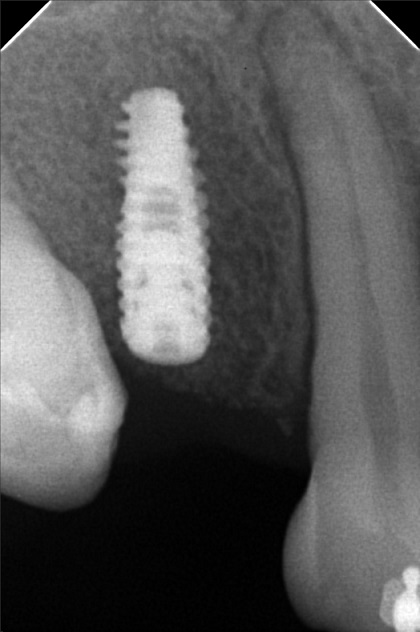

- Procedure

- 07/24/21- IPR23 U to left 09/23/21 16*16ss upper/ 16*16 lower all upper to left LC 11/12 mesial 10/16/21 upper to left S-elastic 16 to 46 fox lower tipping of incisal anterior double chain 11/27/21- adj same wire class 2 elastic force 2 chain upper/ rw 42 02/05/22- same wire 03/20/22- chain upper 16x 16 ss UL/ ind lower/ fox 24-25 to 34-35 04/23/22 - chain upper 4/23/22- same wire/ distalized 16 for implant placement/ 13 to 46 rabbit 06/18/22- adj same wire. class 2 elastic rabbit 08/26/22 - irrigate w/ aquolab; same wire; chain upper; change rw 42 9/19/22 - implant #14 CGF & PRF ( Bio- Oss 0.25-1mm ) implant size -4.0x11.5mm 10/21/22 - UL SAME WIRE/ RPI b/w #43-44, U CHAIN/ REATTACH #36 11/18/22-dpforImplant/adj 1/27/23-ADJ 05/13/23- installation of abutment/Impression taking 06/21/25 OP w/ Air polisher retainer U/L